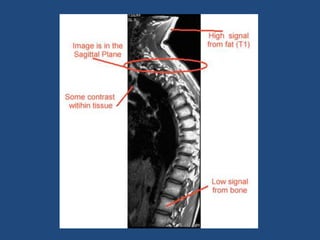

T1 time &T2 Decay are an intrinsic contrast parameter that are inherent to tissue being imaged. T1WI